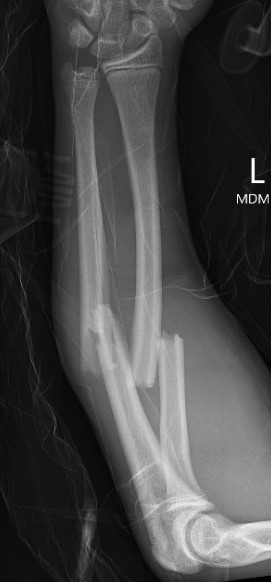

Types

Complete

Greenstick

Buckle / torus

Single or both bone

Galeazzi / Monteggia

Operative Management

Indications

Outside parameters for non-operative treatment (see above)

Loss of reduction

Options for displaced fractures

Single v Double Elastic Nail

Dietz et al. J Pediatr Orthop 2010

- retrospective review of 38 children with both bone forearm fractures

- treated only with ulna elastic nail

- all patients had union with restoration of rotation

- two patients had angulation of the radius > 20 degrees that underwent surgical intervention